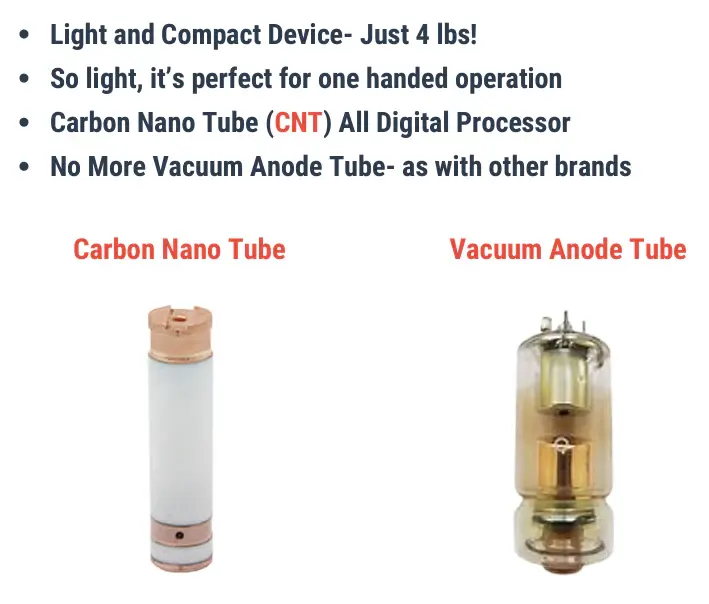

At the heart of the X4 is its cutting-edge Carbon Nano Tube (CNT) technology—a modern alternative to traditional filament-based x-ray tubes. Unlike conventional systems that require high heat to generate electrons, CNT emits electrons instantly, allowing for faster, more energy-efficient exposures. The result? Streamlined workflow, less downtime, and greater consistency with every image.

- Advanced Carbon Nano Tube (CNT) X-ray tube